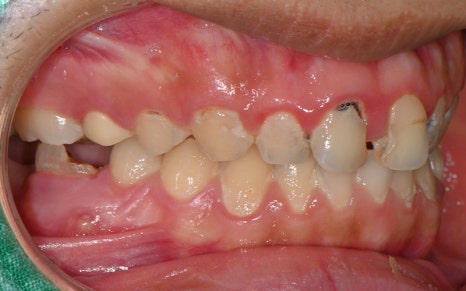

The patient we are introducing had several cavities in progress,

and the pain would come and go,

which made it even easier to miss the right timing for treatment.

As can actually be seen in the treatment record,

more than 10 teeth received

root canal treatment,

and most were accompanied by complex inflammation and nerve infection.

In particular, treatment was carried out across a wide area,

including the upper front teeth and molars.